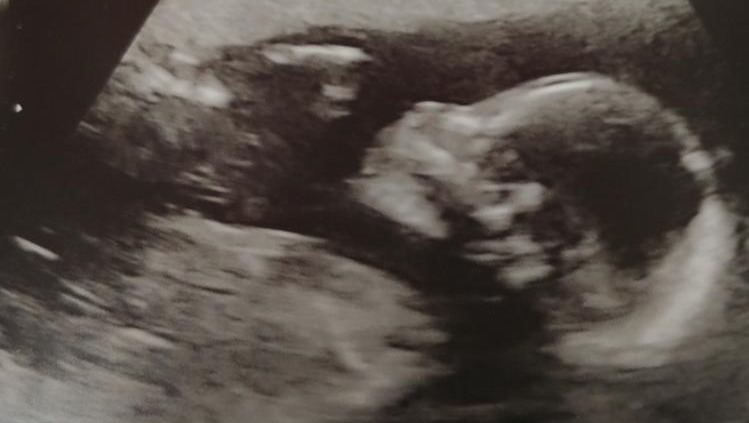

I always thought people fainting from shock or grief was something out of the movies, an exaggeration for dramatic effect, but on July 7th, 2020, I learned in the worst possible way that was not the case. After a beautiful and much wanted pregnancy, an IVF pregnancy that came after years of struggle and heartache and complications, it was revealed at our 20-week ultrasound that something was very wrong with our son.

The visit started with a giddy ultrasound tech suddenly going silent mid-scan. They then ushered me into several empty rooms until finally they took me into one ominously labeled "High Risk Neonatal Consult" where my ultrasound pictures hung across one wall. I could see the news to come on everyone’s faces, and then I saw it for myself. I was alone, COVID protocols leaving my husband to hear the devastating news from our car. The situation was clear. Our son had severe fetal anomalies: his brain, organs, and spine were all affected.

Our Last Photo of Our Son, Waving </3